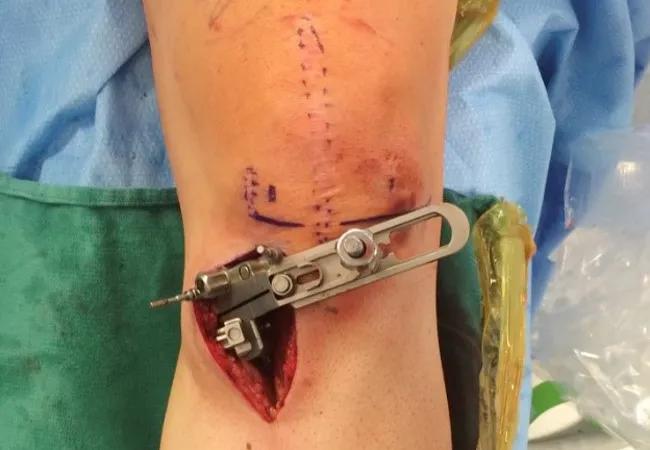

The high tibial osteotomy was performed to shift the weight-bearing line from the medial compartment of the knee to the desired position in the lateral compartment consistent with the preoperative plan. A biplanar cutting jig was used to maintain coronal and sagittal plane deformity correction parameters (Figures 2A & 2B). Final anteroposterior and lateral knee views, and long-limb intra-operative imaging revealed excellent alignment and bone graft technique.

Figure 2. Intraoperative views (2A, 2B) of an intraoperative biplanar alignment jig used to perform accurate high tibial osteotomy correction.